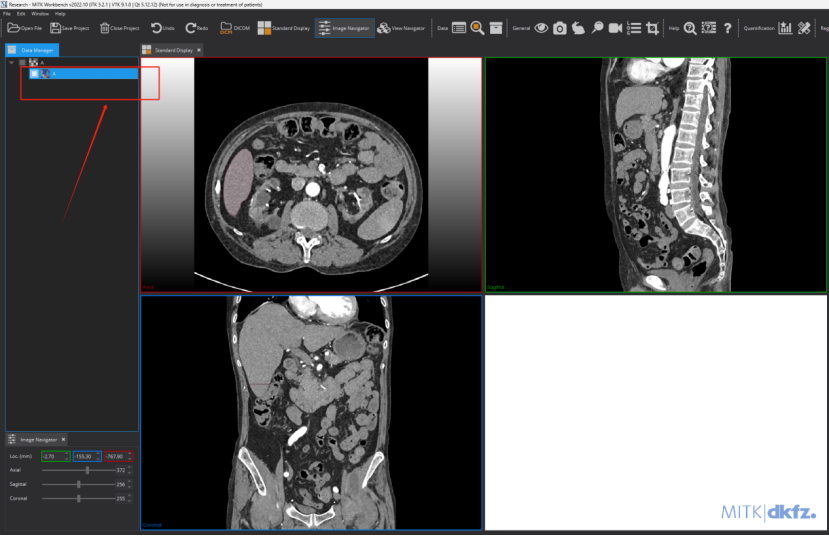

MITK标注

Step 1: 打开MITK,双击桌面的MITK图标

Step 2: 导入图像。即手动将亟待标注的”.nii.gz”文件拖动到下图区域

Step 3: 调节窗宽窗位。有两种方式,手动设置及滑动调节。如果标注肝肿瘤,我手动将窗宽窗位调节到[40-400]

Step 4 进入一个窗口进行标注: 进入单个视图画面更大,更有利于标注。

Step 5: 创建分割。这里需要注意,对create segmentation之后的文件进行重命名操作,具体实现看图片文字说明:

Step 6: 执行标注。按照图片的指示进行操作

点击之后可以进行标注了,这个地方可选择的标注工具比较多,下图框出部分即为标注相关工具,标注者需要进行摸索尝试一下!需要用什么标注工具,选择一下即可,然后在图上进行标注及修改